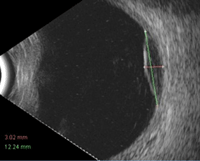

Son tumoraciones benignas complicadas de valorar mediante ecografía, por su poca altura. Los ultrasonidos son útiles en el control evolutivo para evaluar si presentan crecimiento. Se caracterizan por tener una reflectividad alta y una estructura interna homogénea (Figura 6).

Figura 6. Nevus coroideo